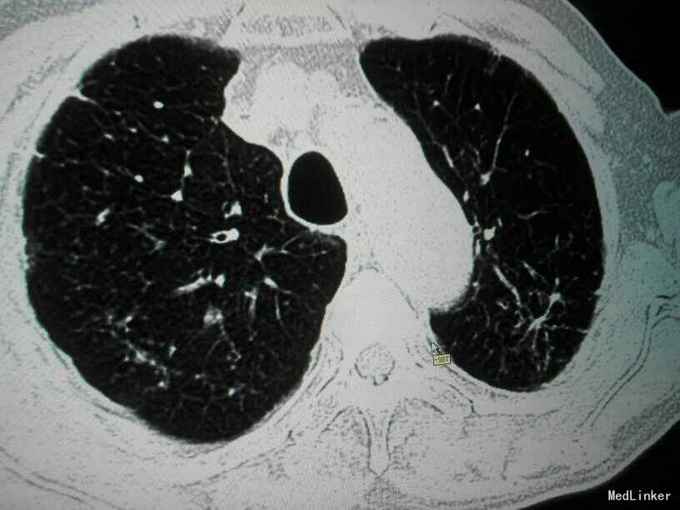

查体:唇指发绀,桶状胸,肋间隙增宽,双肺叩诊呈过清音,双肺呼吸音粗,可闻及散在干湿性啰音,未闻及明显湿性罗音,呼气延长,心腹阴性,双下肢轻度水肿。 辅助检查:入院后血气分析 PH 7.41 PCO2 43mmHg,PO2 73mmHg,BE 2.7mmol/L SO2:96%;心电图:室性早搏;胸片:符合慢支合并双肺炎症;肺CT示1.两肺多发支气管扩张并感染2.两肺间质纤维化,两侧胸膜增厚;心脏彩超:肺动脉压增高,肺动脉略宽;痰培养:肺炎克雷伯杆菌亚种;

诊断:慢阻肺急性发作;支气管扩张并感染;肺间质纤维化;慢性肺心病 治疗经过:抗炎:哌拉西林他唑巴坦;化痰:羧甲司坦口服液+盐酸氨溴索针;解痉平喘:多索茶碱,复方异丙托溴铵雾化溶液+布地奈德雾化混悬剂,雾化吸入;扩冠、减轻心脏负荷:硝酸甘油针;利尿:拖拉塞米针;3日后停硝酸甘油,改单硝酸异山梨酯缓释片口服,后患者出现胸闷、胸痛、气短症状加重,请心内科会诊后,给予呋塞米20㎎,隔日1次口服;螺内酯片20㎎,1日1次;替米沙坦片40㎎ 1日1次;美托洛尔6.25㎎;氯化钾缓释片 0.5g,1日2次;并给予抗血小板聚集、调脂、稳定斑块等治疗;治疗10天后,患者受凉后出现畏寒、发热,侧体温38.1℃,停哌拉西林他唑巴坦,改为盐酸莫西沙星针0.4g,1日1次,其余治疗同前;治疗3天后患者体温恢复正常,偶有咳嗽,咳少量白色黏痰,症状好转,出院。